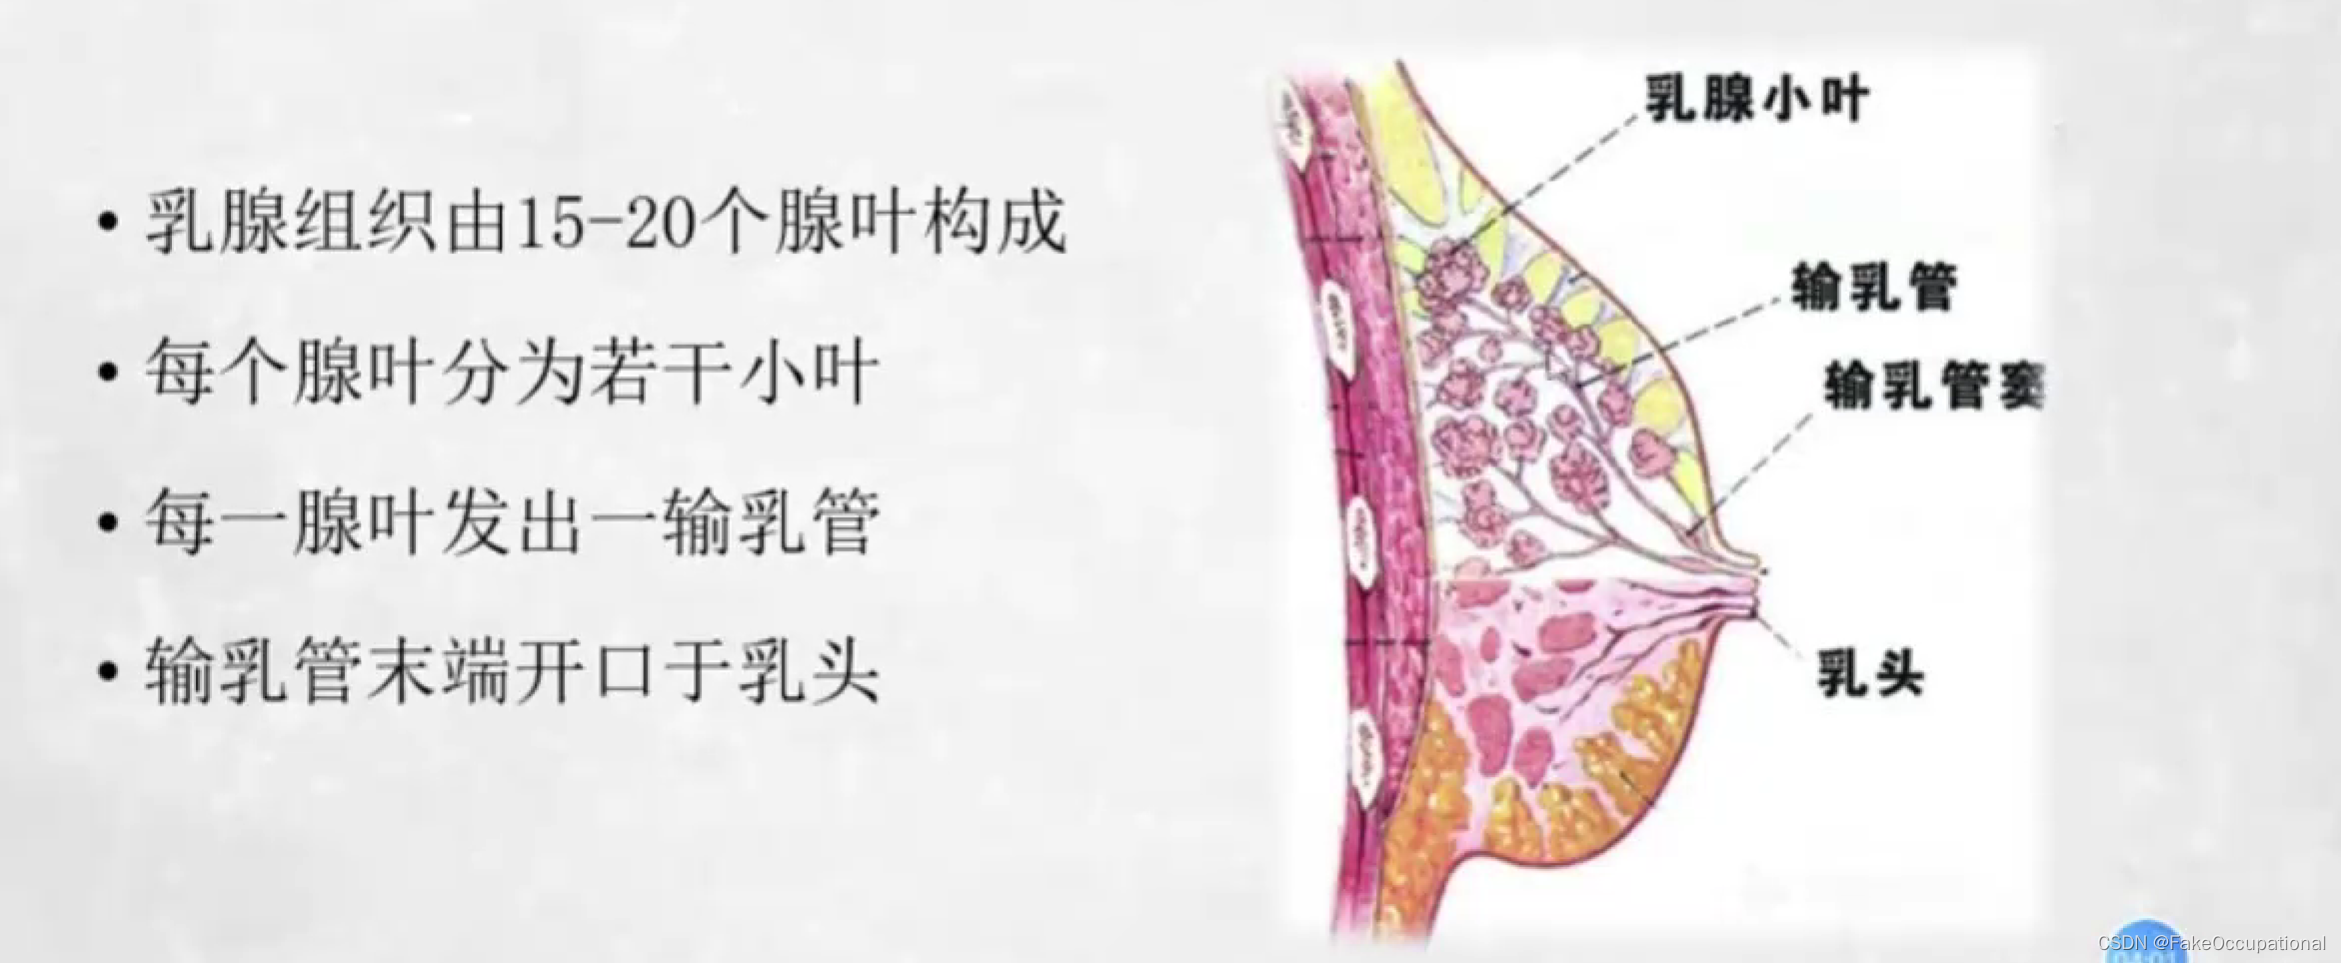

乳腺的生理解剖概要

乳腺的生理解剖概要